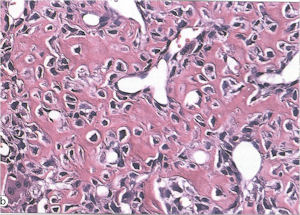

Microscopic Pathology

- Interlacing network of bone trabeculae in a loose fibrovascular stroma

- Prominent vessels

- Osteoblasts are plump, active, scattered mitotic figures

- Osteoblasts line up around periphery of trabeculae (Osteoblastic Rimming)

- Soft tissue component usually surrounded by shell of reactive bone or periosteum (Egg Shell Rim of Calcification)

- No cartilage production (as opposed to osteosarcomas that may contain areas of cartilage)